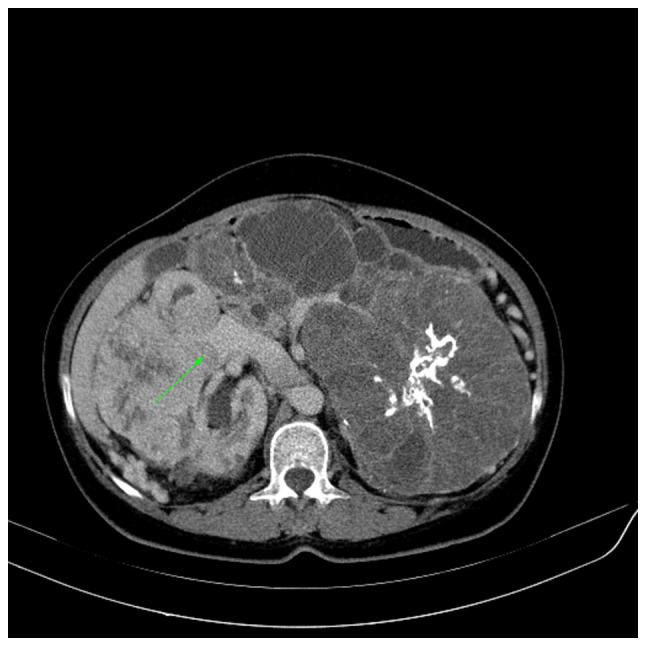

肾细胞癌T分期:术前增强计算机断层扫描的诊断准确性

Renal cell carcinoma (RCC) accounts for 1-2% of all malignancies and is the most common renal tumor in adults. Imaging studies are used for diagnosis and staging. Tumor-Node-Metastasis staging strongly affects prognosis and management, while contrast-enhanced computed tomography (CECT) is regarded as a standard imaging technique for local and distant staging. The present study aimed to evaluate the accuracy of CECT for the preoperative staging of RCC by using surgical and pathological staging as the reference methods. This single-center prospective study was conducted between October 2019 and November 2021. The preoperative abdominal CT scans of patients suspected of having RCC were reviewed. Imaging data were collected, including tumor side and size, and perinephric fat invasion. Intraoperative notes were recorded, including the operation type, perinephric fat invasion, renal vein (RV) or inferior vena cava (IVC) tumor extension, and surrounding organ invasion. pathological data were collected on tumor size, RCC type, presence of clear margins, presence of renal capsule or perinephric fat invasion, renal sinus or pelvicalyceal system (PCS) invasion, segmental or main RV extension, and the involvement of Gerota's fascia and nearby organs. Preoperative CECT revealed that 42 out of 59 tumors had a greater maximum diameter than the pathological specimen, with an overall disparity of 0.25 cm. The specificity of CT for the detection of tumor invasion of the perinephric and renal sinus fat and PCS was 95%, and the sensitivity ranged from 80 to 88%. CT had an 83% sensitivity and a 95 specificity in detecting T4 stage cancer, with a 100% specificity for adrenal invasion. The concordance between radiographic and histological results for RV and IVC involvement was high, with specificities of 94 and 98%, and sensitivities of 80 and 100%, respectively. Overall accuracy for correct T staging was 80%. In conclusion, CECT is accurate in the local T staging of RCC, with high sensitivity and specificity for estimating tumor size and detecting extension to nearby structures and venous invasion.

肾细胞癌(RCC)占所有恶性肿瘤的1%-2%,是成人中最常见的肾脏肿瘤。影像学检查用于诊断和分期。肿瘤-淋巴结-转移分期对预后和治疗有很大影响,而对比增强计算机断层扫描(CECT)被视为局部和远处分期的标准影像学技术。本研究旨在以手术和病理分期作为参考方法,评估CECT对RCC术前分期的准确性。这项单中心前瞻性研究于2019年10月至2021年11月进行。对疑似患有RCC患者的术前腹部CT扫描进行了回顾。收集了影像学数据,包括肿瘤侧别和大小以及肾周脂肪浸润情况。记录了术中情况,包括手术类型、肾周脂肪浸润、肾静脉(RV)或下腔静脉(IVC)肿瘤延伸以及周围器官浸润情况。收集了病理数据,包括肿瘤大小、RCC类型、切缘情况、肾包膜或肾周脂肪浸润情况、肾窦或肾盂肾盏系统(PCS)浸润情况、节段性或主RV延伸情况以及肾周筋膜和附近器官的受累情况。术前CECT显示,59个肿瘤中有42个的最大直径大于病理标本,总体差异为0.25厘米。CT检测肾周和肾窦脂肪及PCS肿瘤浸润的特异性为95%,敏感性范围为80%-88%。CT检测T4期癌症的敏感性为83%,特异性为95%,对肾上腺浸润的特异性为100%。对于RV和IVC受累情况,影像学和组织学结果之间的一致性较高,特异性分别为94%和98%,敏感性分别为80%和100%。正确T分期的总体准确率为80%。总之,CECT在RCC的局部T分期中是准确的,在估计肿瘤大小以及检测向附近结构的延伸和静脉侵犯方面具有高敏感性和特异性。